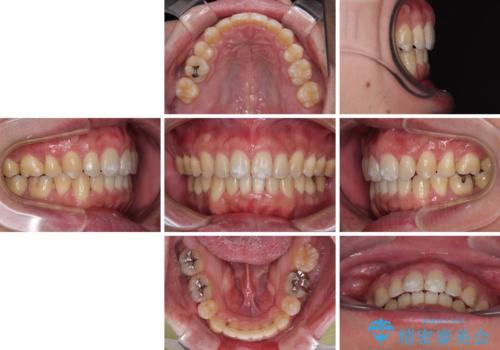

2年から2年半の治療期間を想定しており、予定通りの期間で無事に終了することができました。

唇や顎先に力を入れないなくてもスムーズに唇を閉じることができるようになりました。